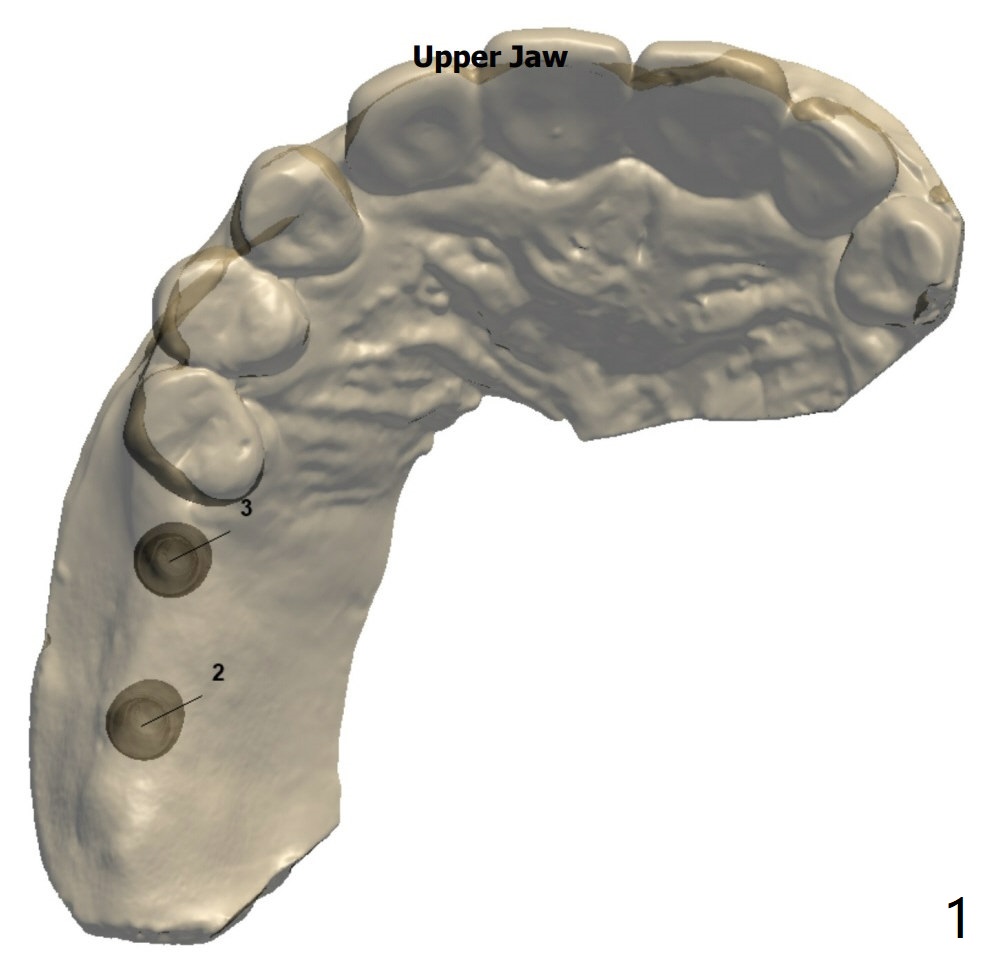

Narrow Implants with Lift